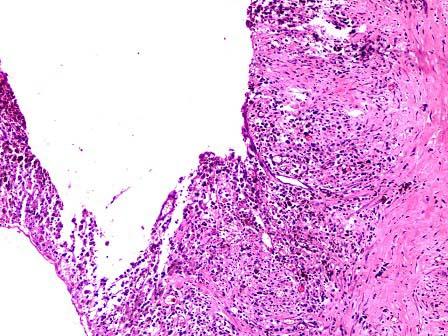

问题 女性,37岁,月经不规则数年,因下腹痛行检查,发现左下腹一包块。行左侧卵巢切除术并送检。大体见卵巢组织间一囊性瘤5cm×4cm×2cm,灰红,切开流出红褐色粘稠液体,囊壁增厚,壁厚12cm。镜下见囊壁增厚,纤维组织增生,无明显内衬上皮,可见含铁血黄素。卵巢组织间见子宫内膜上皮与间质结构(如图)。应诊断为 ( )

选项 A.卵巢巧克力囊肿 B.卵巢黏液性囊腺瘤 C.卵巢交界性黏液性囊腺瘤 D.卵巢黏液性囊腺癌 E.卵泡膜囊肿

答案 A